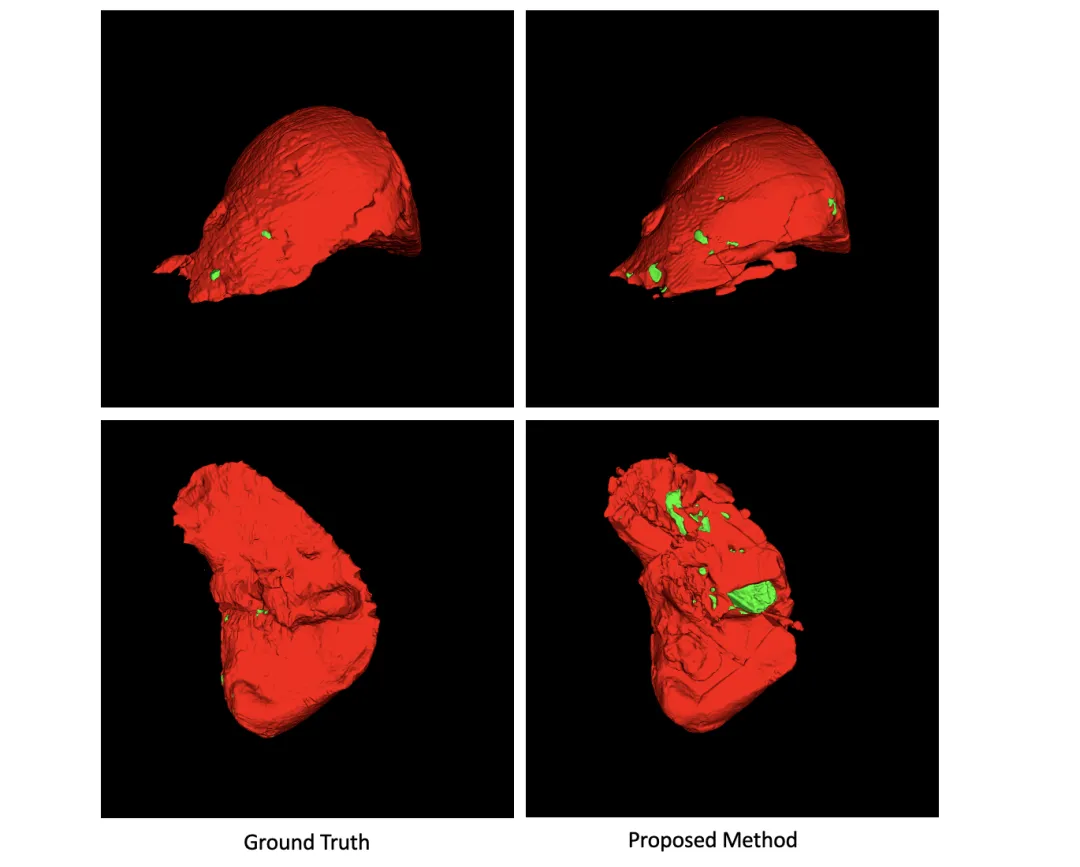

视觉与定量结果一致:可视化结果显示,所提方法的分割结果与真实标注高度吻合,尤其在细小肿瘤和复杂边界的处理上表现优异,3D重建体积平滑且解剖结构合理,符合手术规划与定量评估的临床需求。

图4:3D重建结果与真实标注的视觉对比